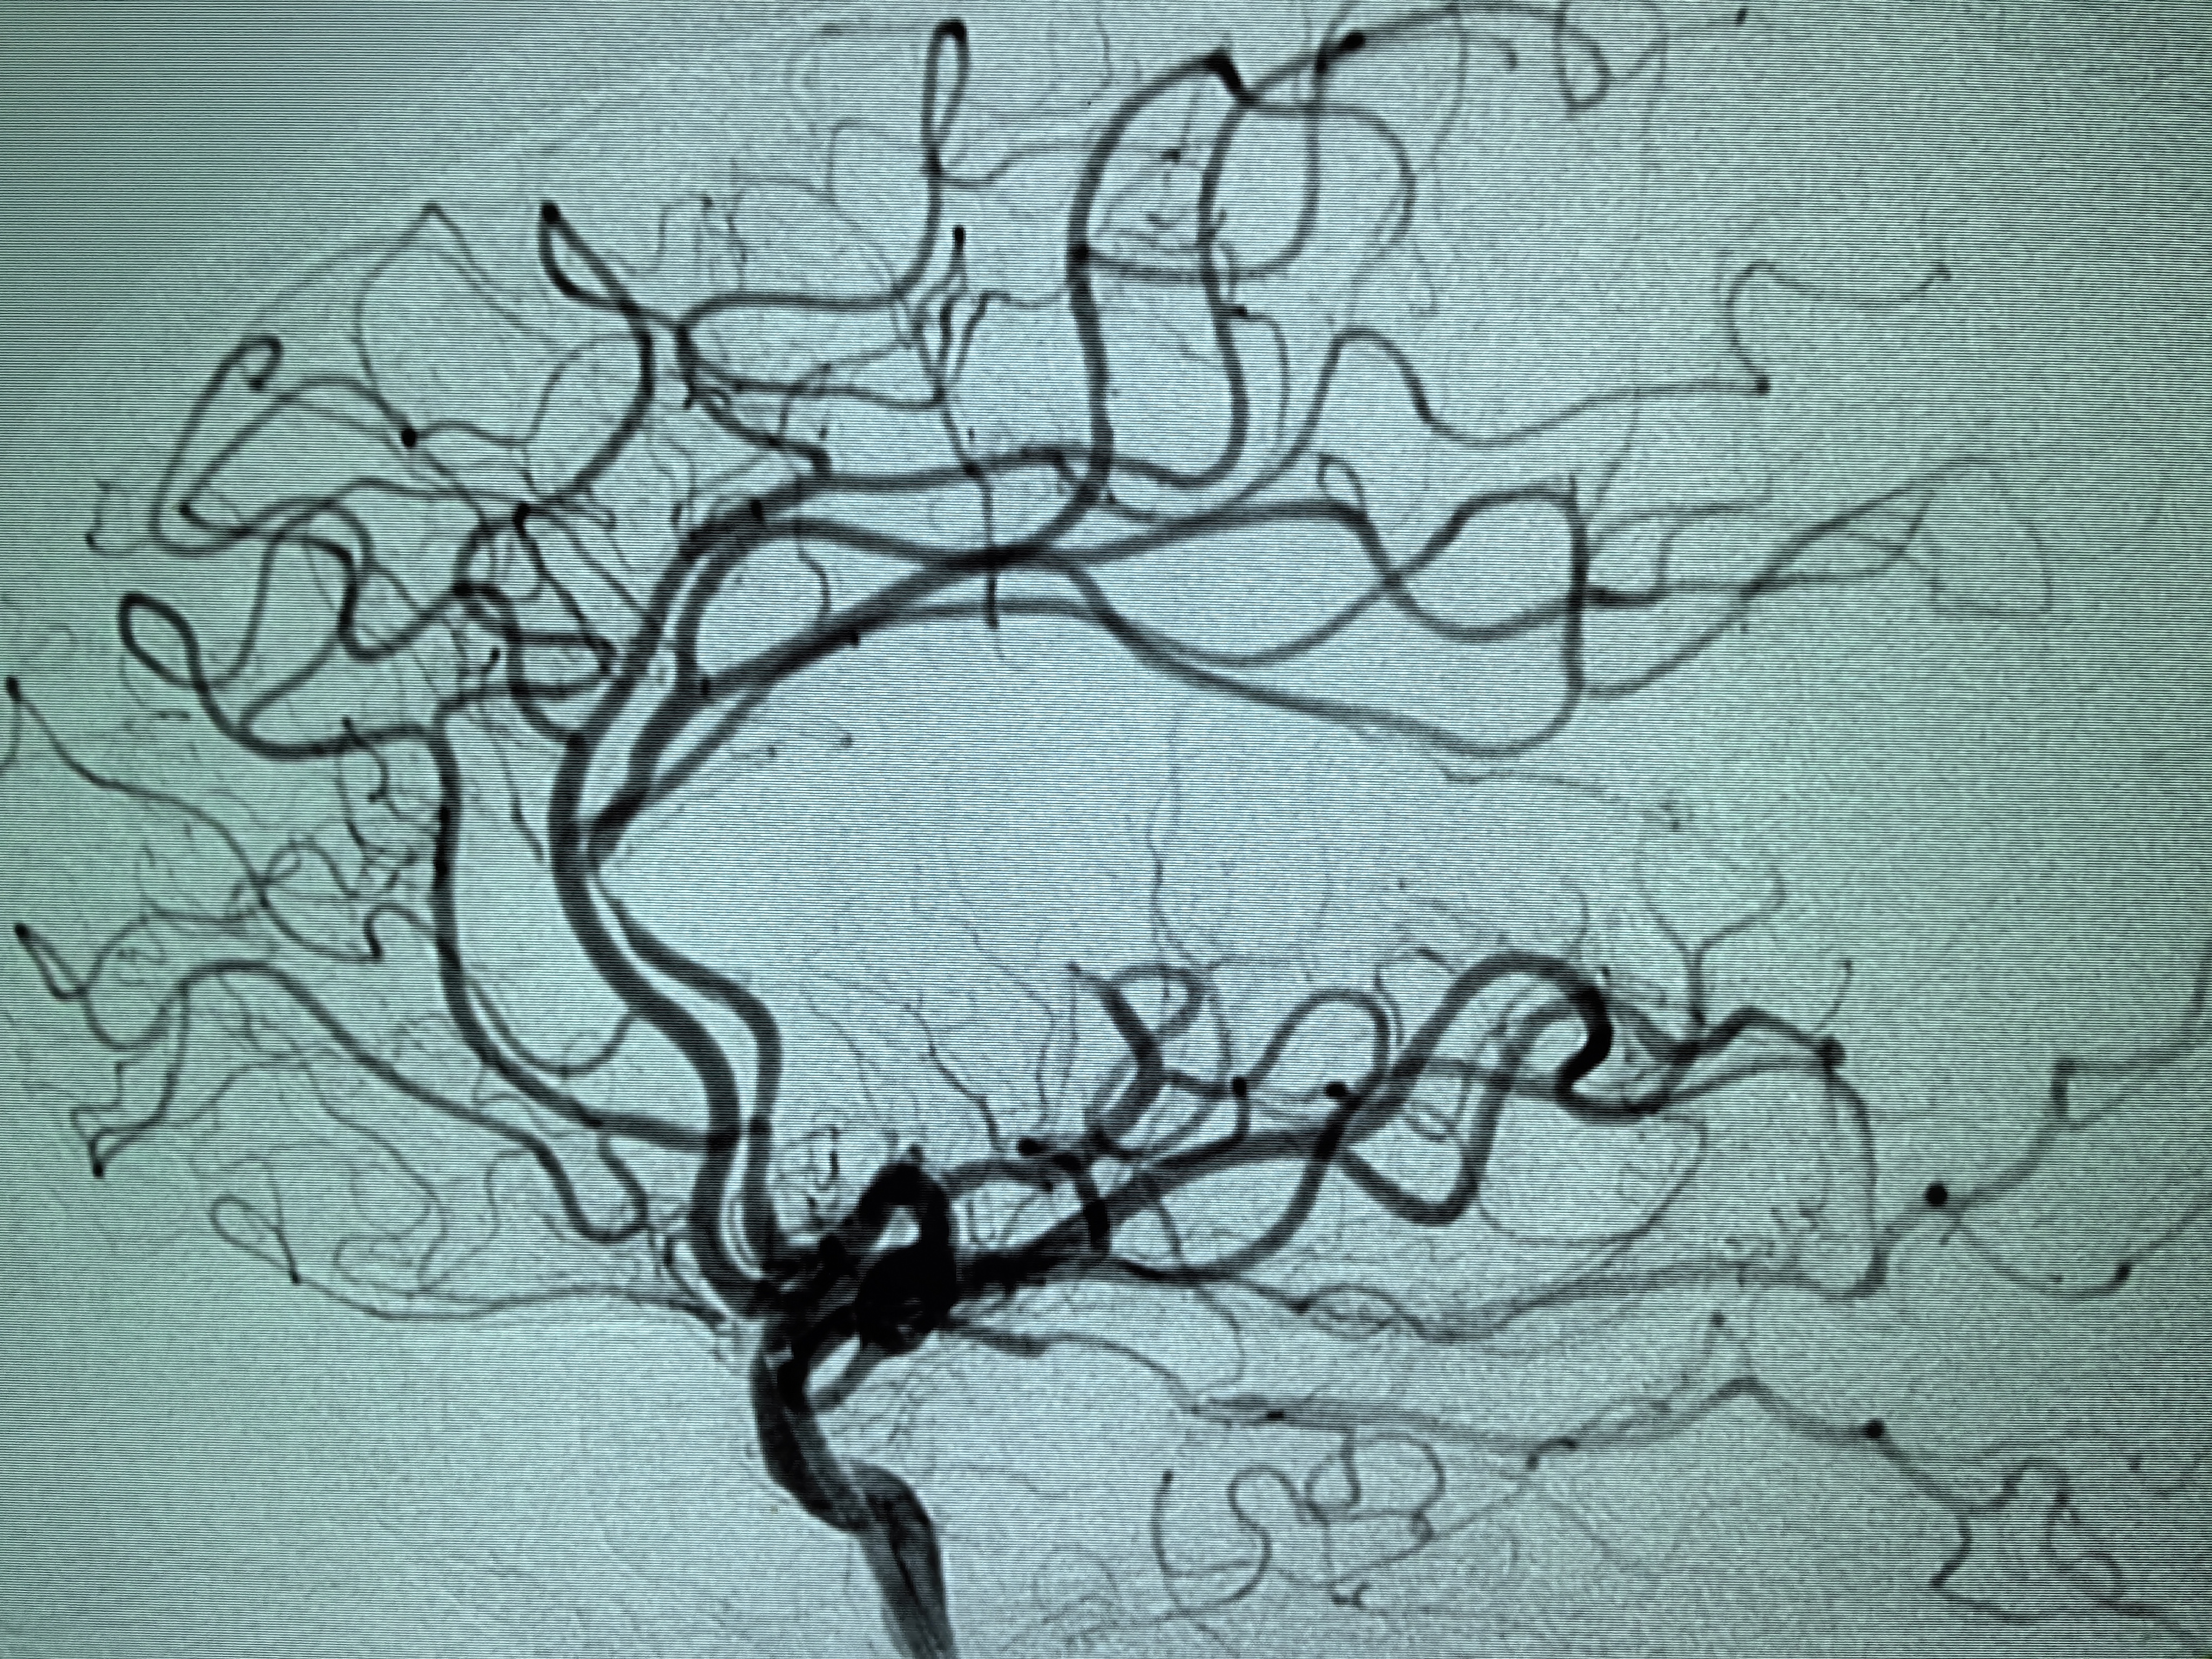

1、本例患者老年女性,系骨科术后次日醒后卒中,经核磁评估提示左侧大脑中动脉闭塞,系责任血管,患者心电图示房颤,考虑心源性栓塞可能性大。

2、本例患者SWIM技术取栓一次后血管再通,颅内血流通畅。